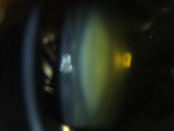

Klare Linse ohne Linsentrübungen

Katarakt („Grauer Star“)

Eine Katarakt (links) verursacht ein unscharfes Bild durch vermehrte Lichtstreuung. Ein Linsentausch (rechts)  korrigiert den Abbildungsfehler.